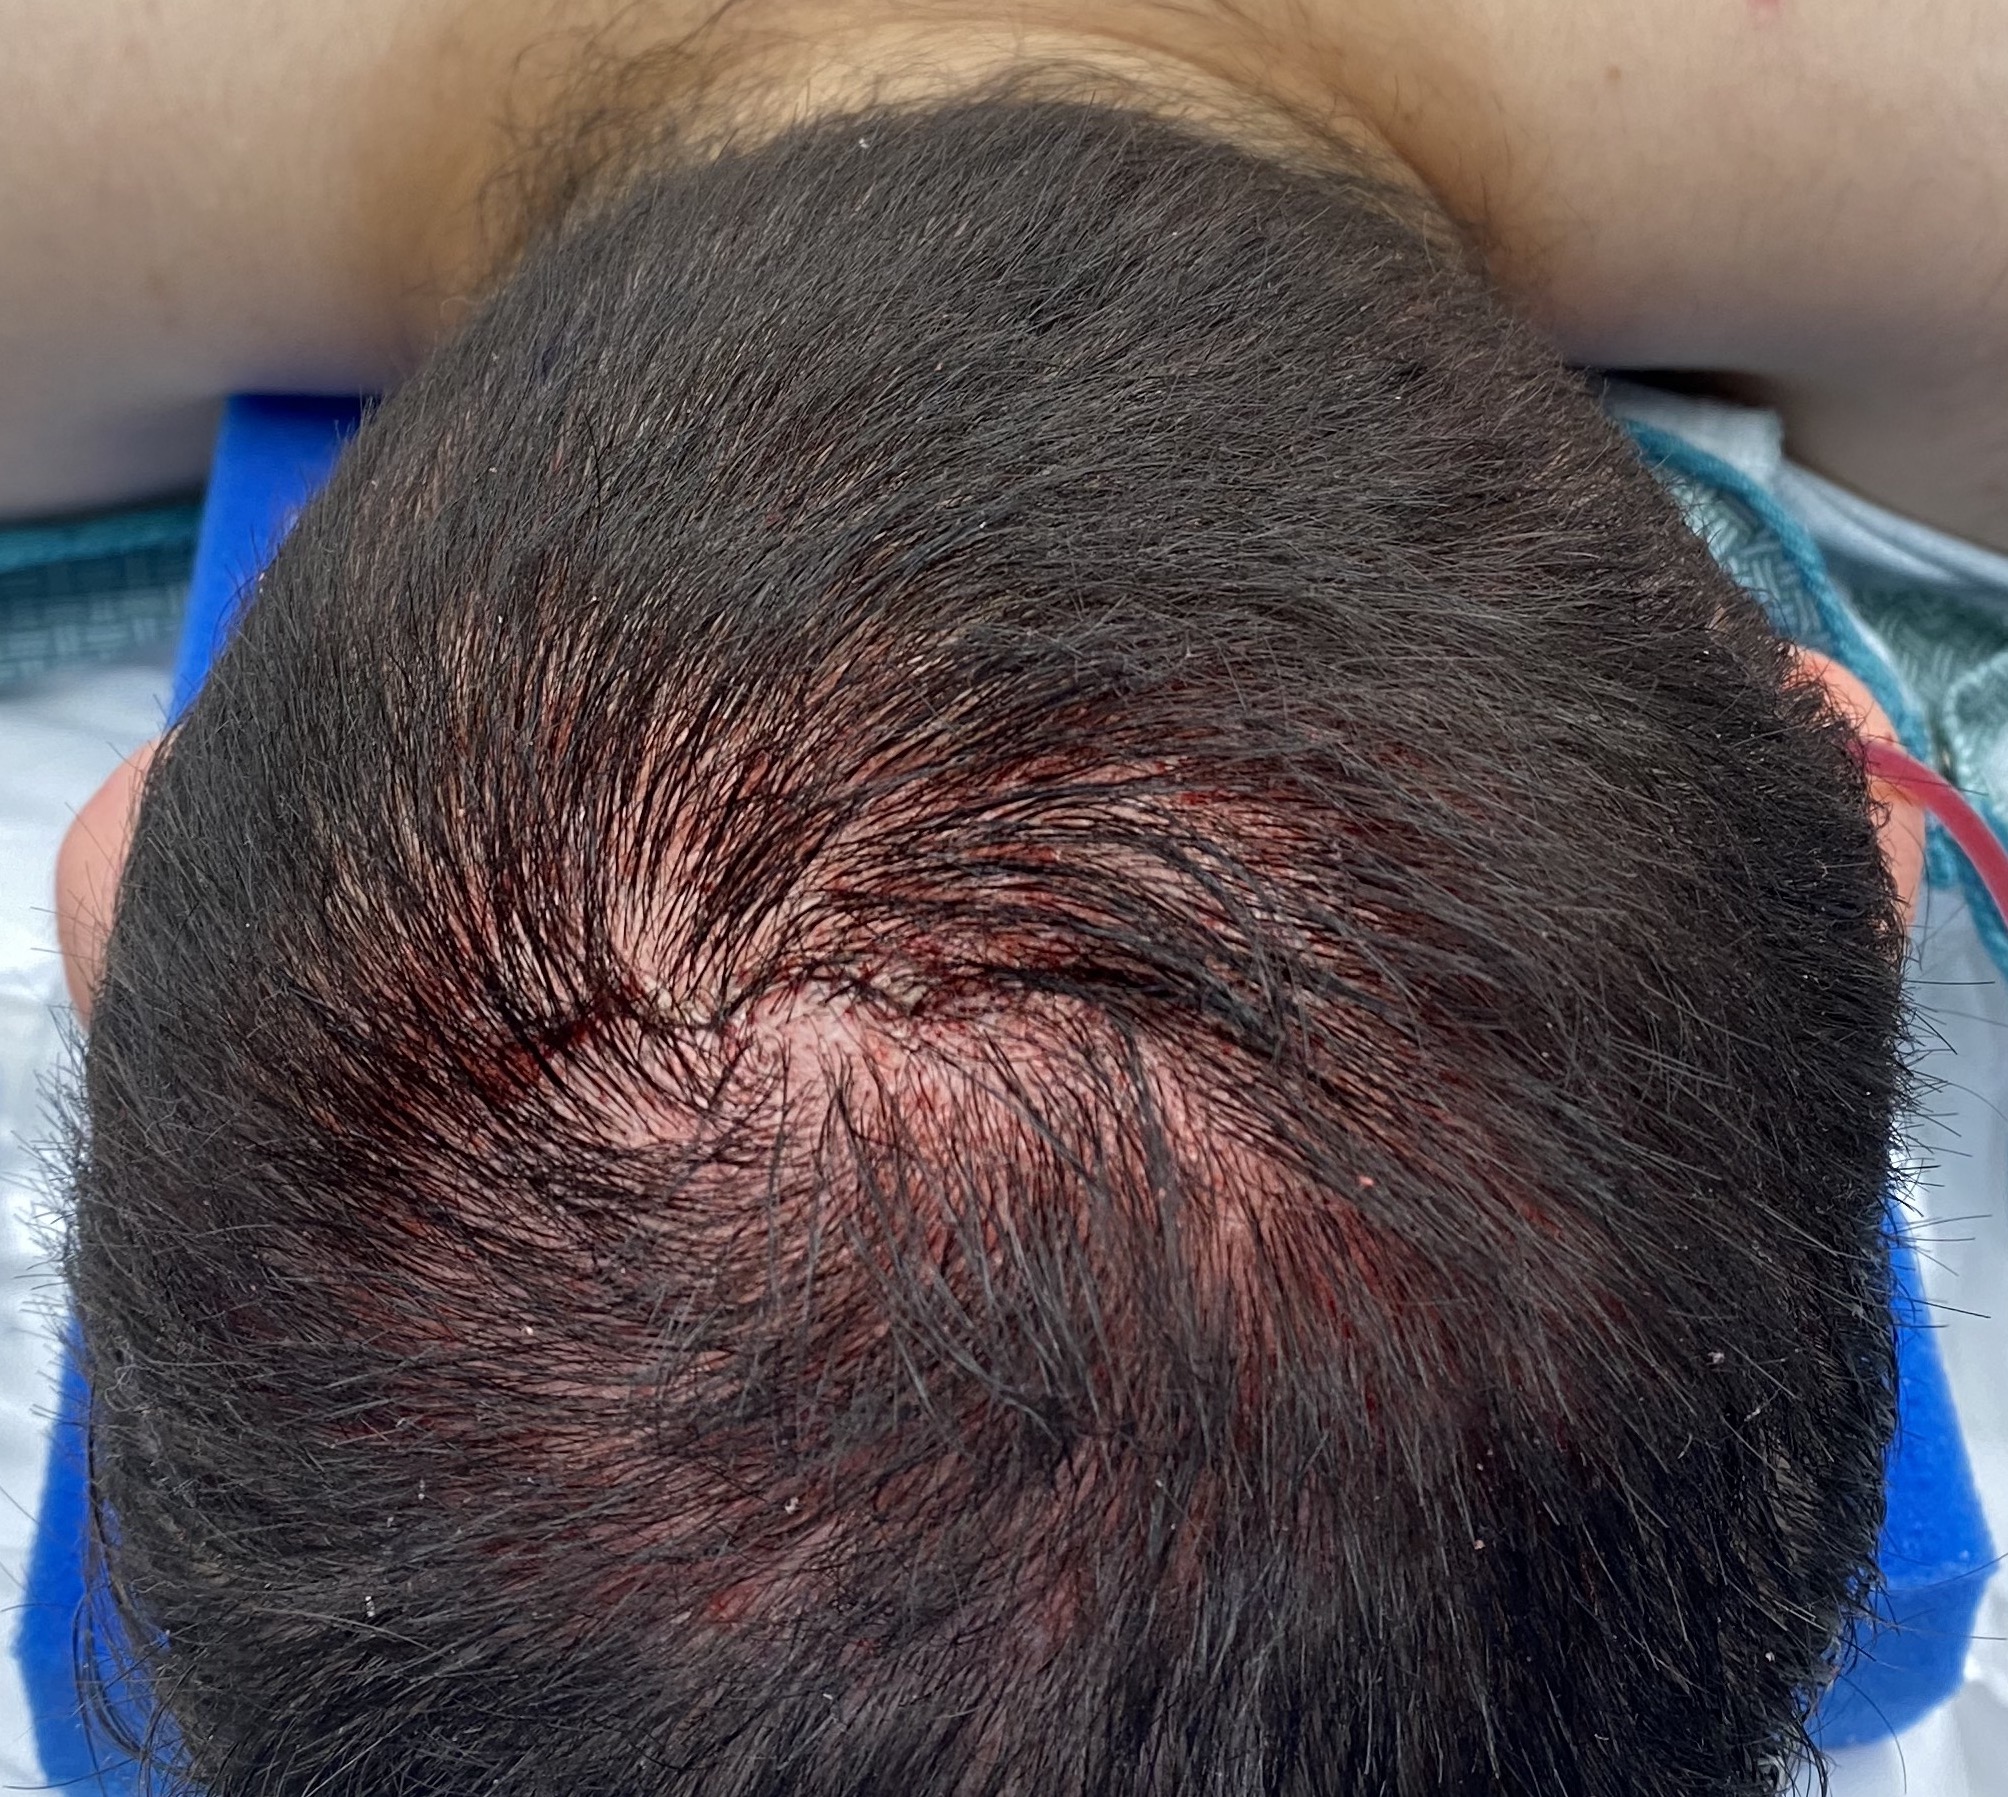

Scalp avulsion due to traumatic injury which left a large patch of non-hair bearing scalp.

Hair bearing scalp reconstruction using a first stage tissue expanders and second stage scalp scar removal.

Scalp avulsion due to traumatic injury which left a large patch of non-hair bearing scalp.

Hair bearing scalp reconstruction using a first stage tissue expanders and second stage scalp scar removal.